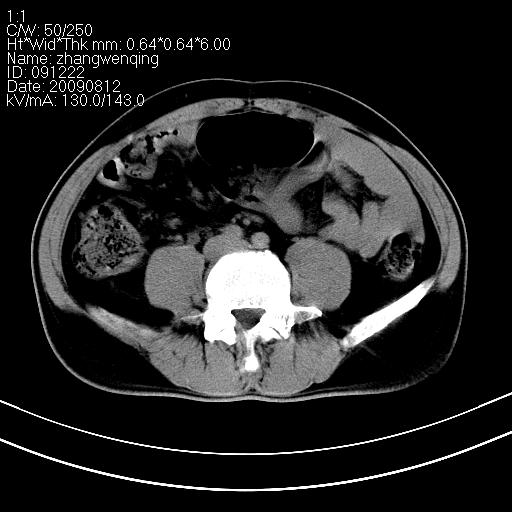

标题: CT21569:M,54Y,右侧中腹部疼痛,IVP示右侧输尿管中下段充盈缺 [打印本页]

标题: CT21569:M,54Y,右侧中腹部疼痛,IVP示右侧输尿管中下段充盈缺

右输尿管下段扩张积水。左下腹部肠管间质瘤不除外。

看不清,应打个增强,右侧输尿管扩张,右侧肠系膜上好像占位。

右侧输尿管扩张积水,考虑结石,最好做个增强除外输尿管占位性病变

支持右侧输尿管中下段扩张积水,建议增强排除占位。

右输尿管下段扩张积水,壁增厚、边缘不光整,考虑炎性改变

ct21569和ct21569b(增强)结果:阑尾腺癌,侵犯回盲部及输尿管中段。手术切除部分升结肠、回肠及受侵4cm之输尿管,做回-横结吻合,输尿管支架置放术并吻合,术后病理腺癌,阑尾来源可能性大。

右侧输尿管扩张似见软组织密度影,输尿管占位不能排除。